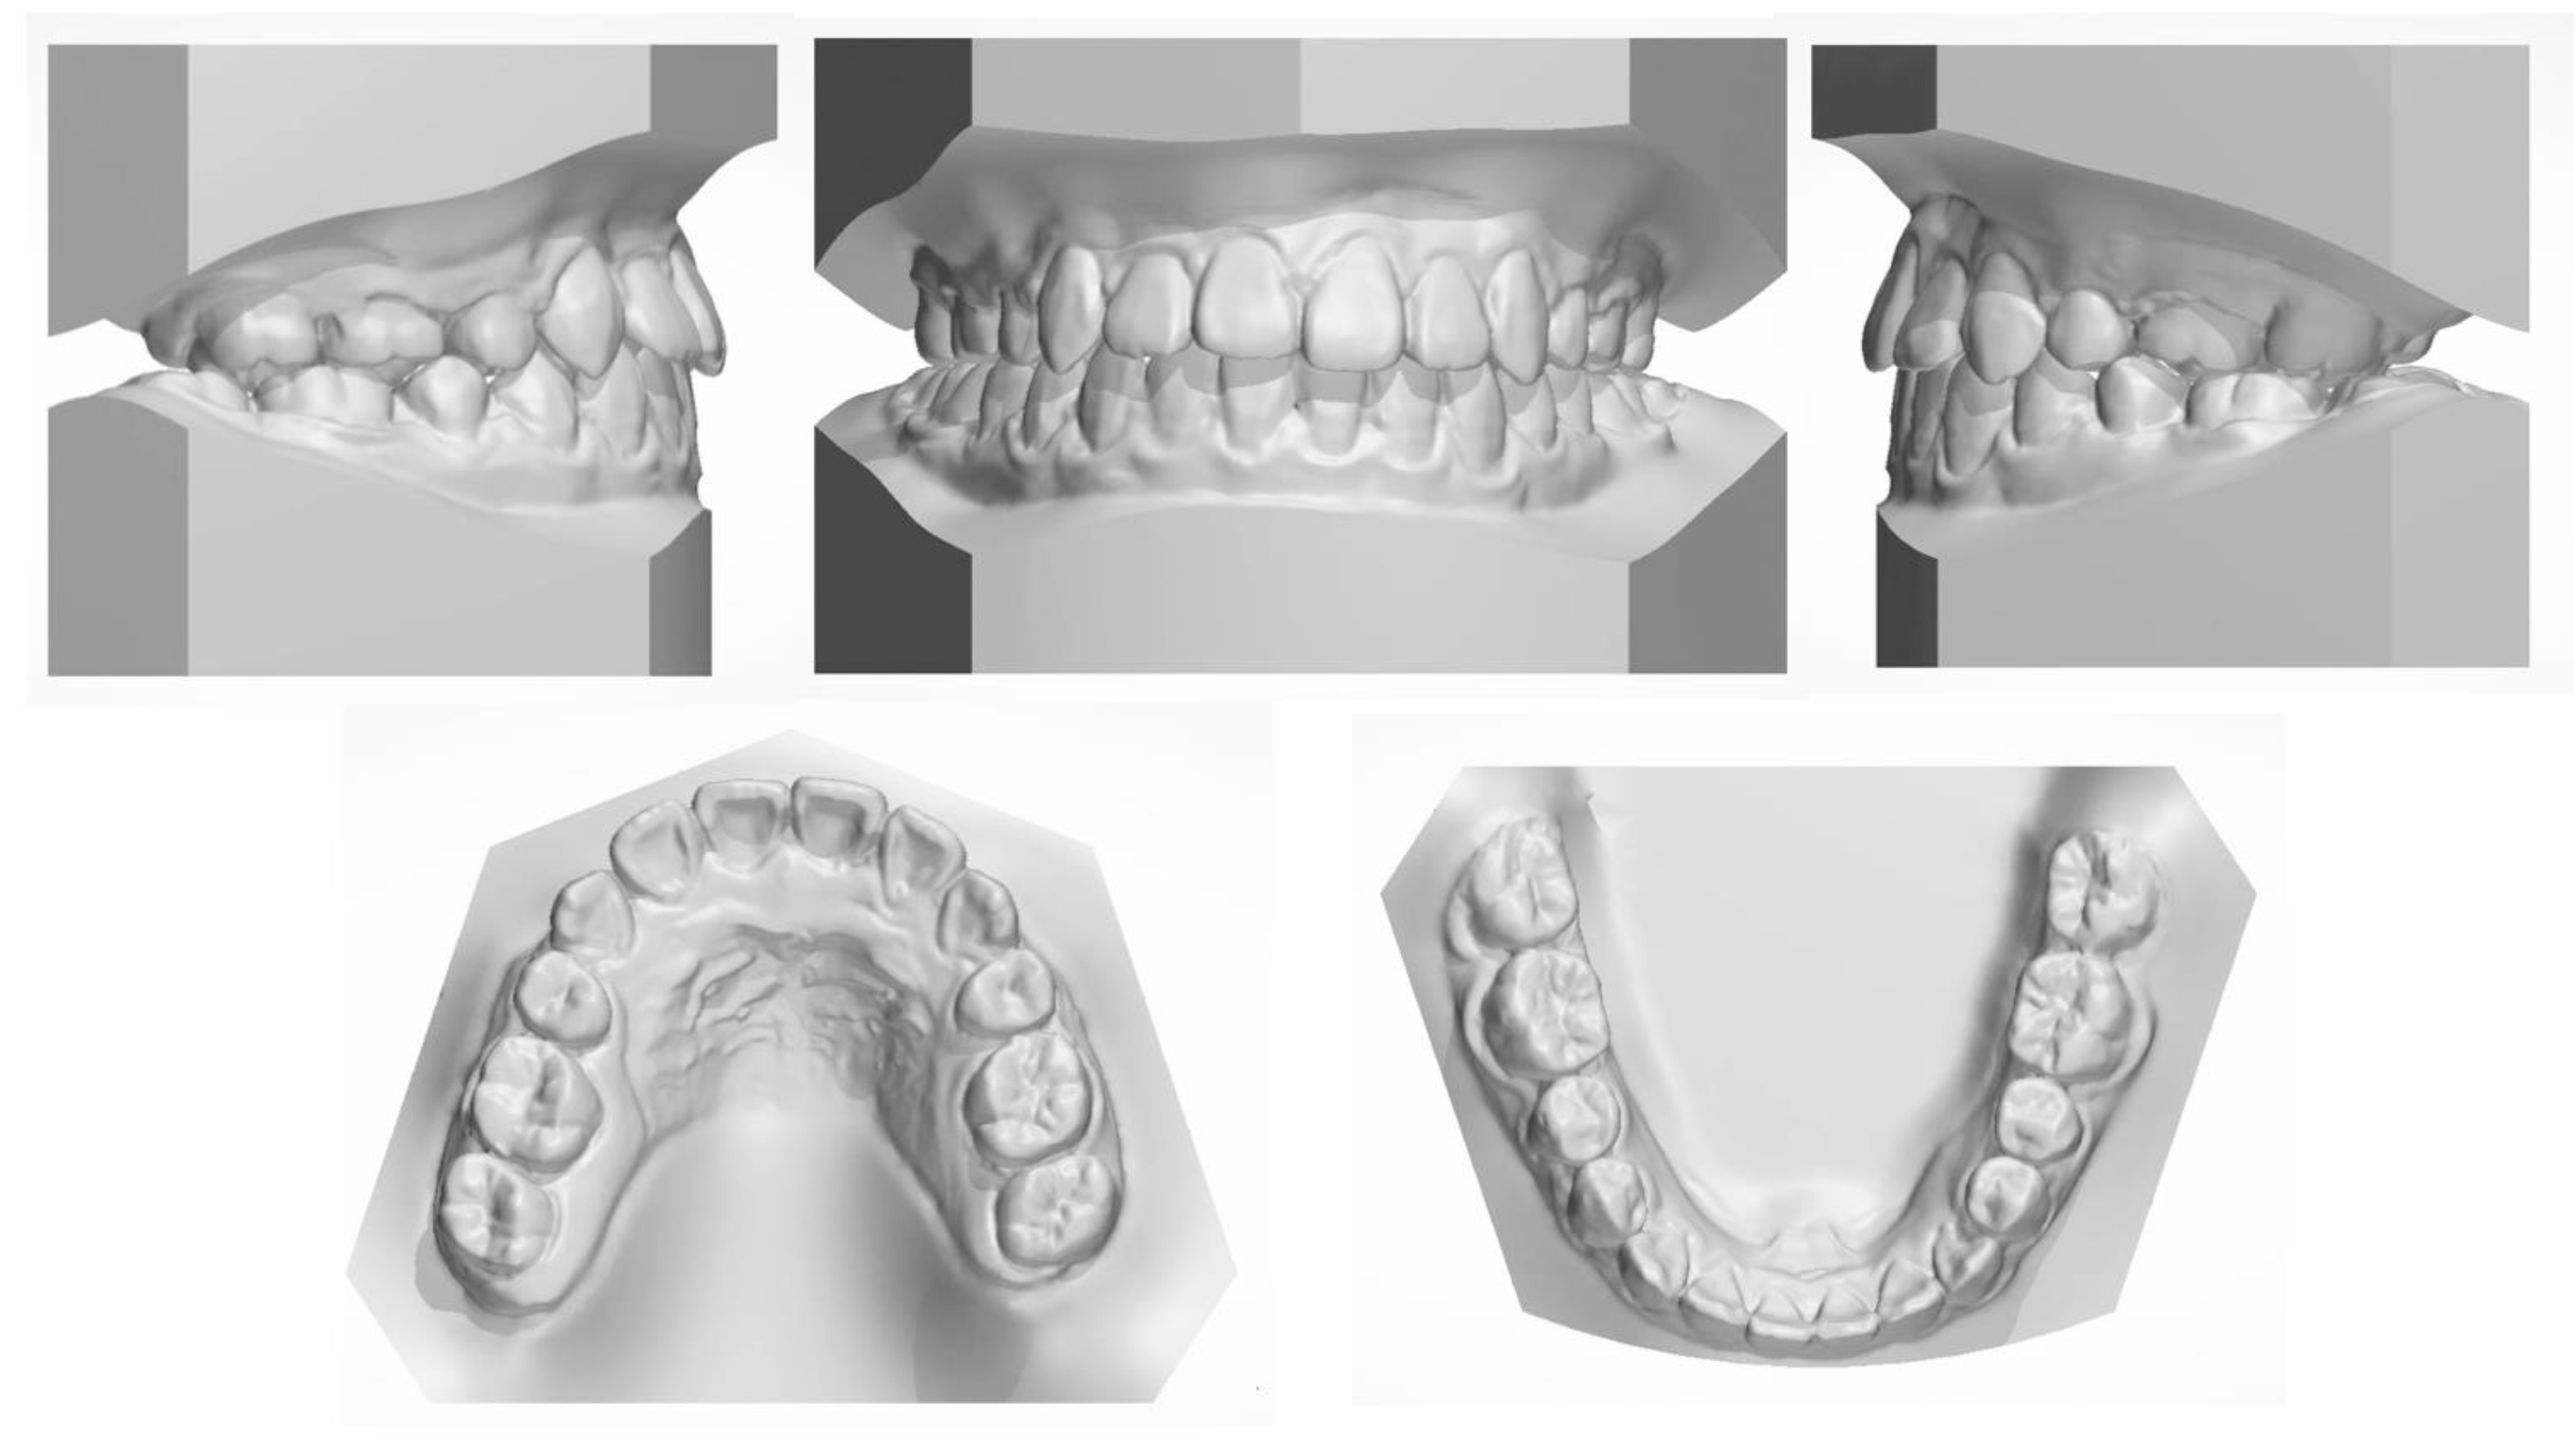

Figure 8. Posttreatment dental casts.

All the initial treatment objectives, including occlusion, periodontal health, and facial esthetics, were achieved by a satisfactory multidisciplinary approach, partly due to the cooperation of the patient. The facial photographs showed a pleasant profile and a harmonious smile. The patient was satisfied with the facial improvement, and she became more confident (Figure 7). Posttreatment intraoral photographs and dental casts (Figure 8) showed bilateral Class II molar and Class I canine relationships with an ideal overjet and overbite. The gingiva tissue in the mandibular anterior region was evidently augmented, which indicated lower periodontal risks.

The final panoramic radiograph confirmed parallel roots with no apparent root resorption. Cephalometric analysis (Figure 9 and Table 1) indicated a normal anteroposterior (AP) relationship (ANB, from −4° to 1.3°) and decreased lower third (FMA: from 26.6° to21.5°; Na-Me: from 111.8 mm to 103.7 mm). Furthermore, the distance from the upper and lower lips to the E-line were significantly decreased, which helped improve the soft tissue profile.